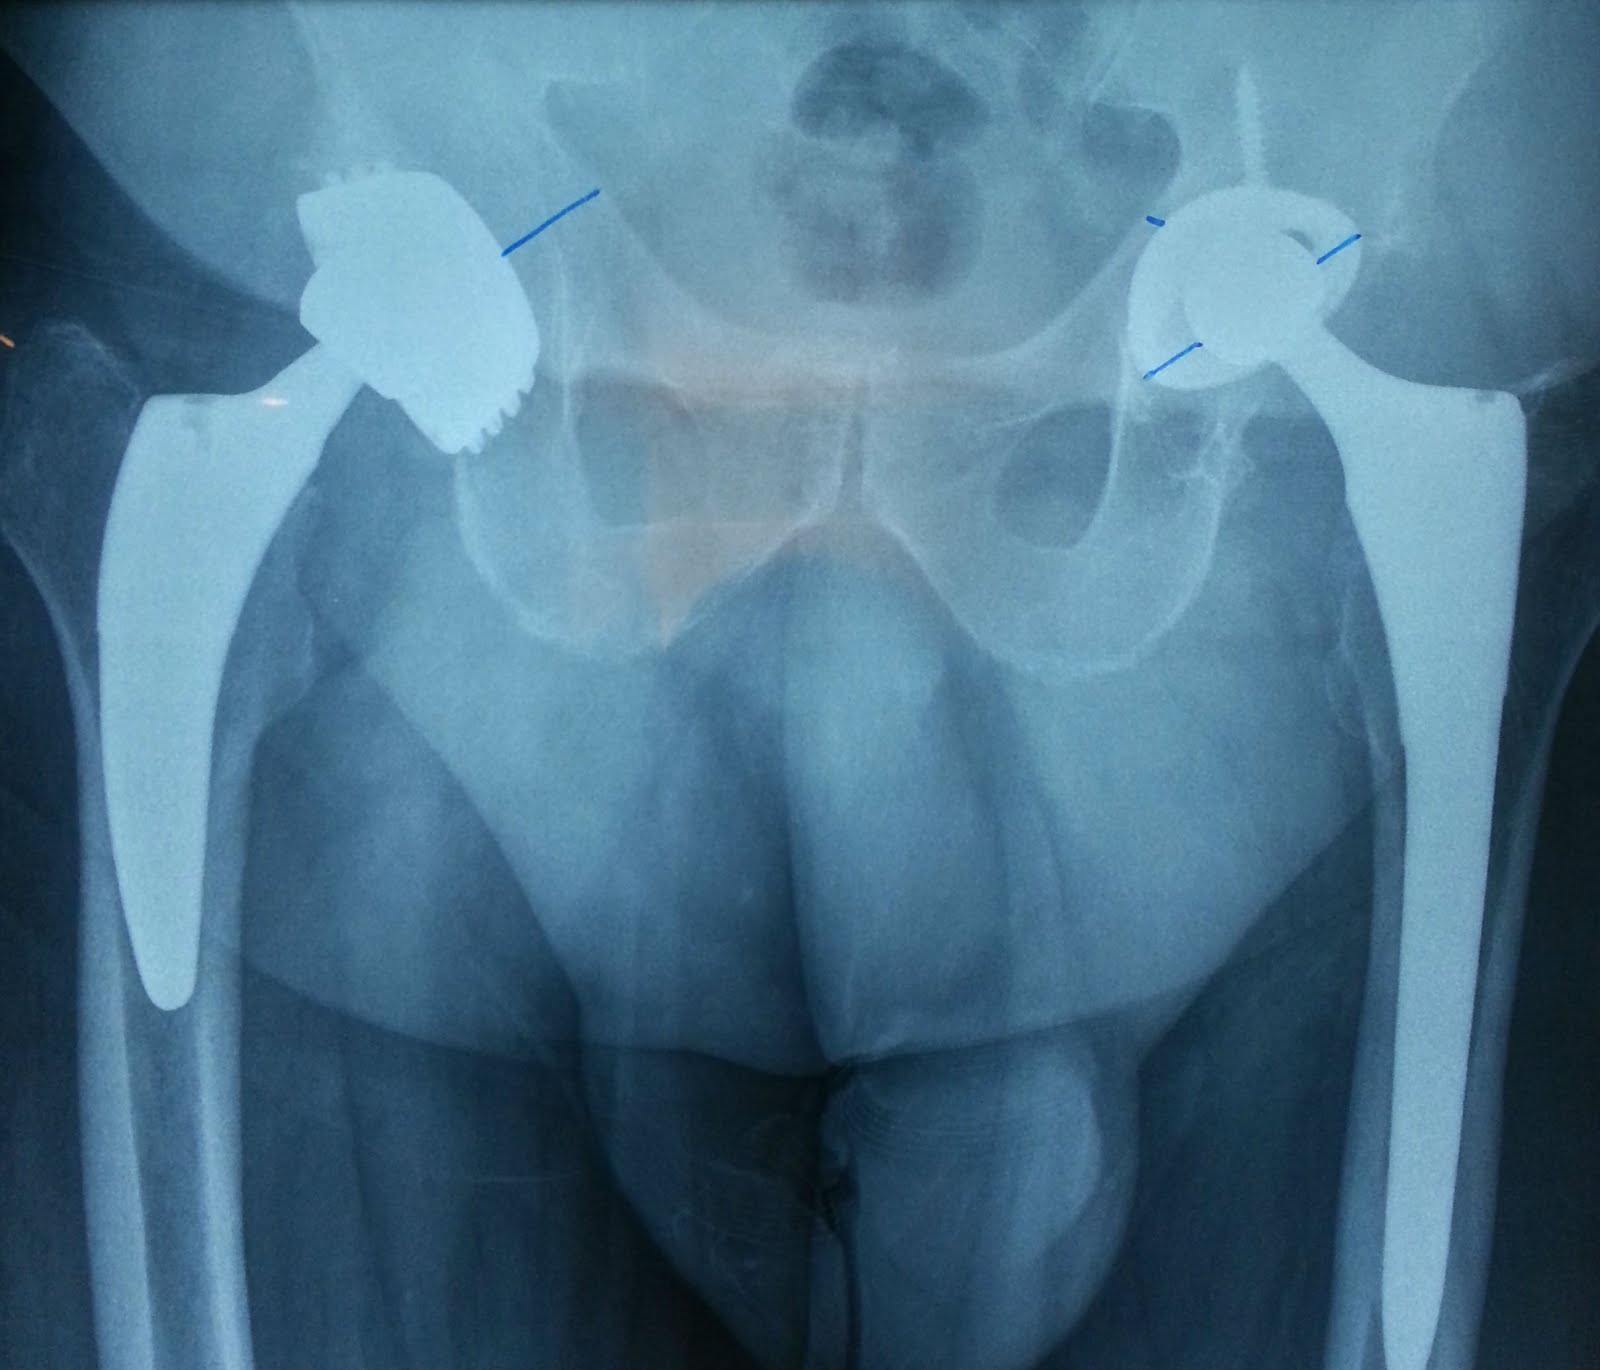

Xray Both Hip Ap View Showing Right Hip Replacement Or Hip Prosthesis Titanium Hip Replacement Problems Symptoms of a loose hip replacement include pain in the groin or upper. You’ve recently had a hip replacement and you have: Throbbing or cramping pain in your hip or leg; A loosening hip replacement implant can be painful. The most common problem that can arise as a result of a hip replacement is loosening of the joint. If your. Titanium Hip Replacement Problems.

From www.alamy.com

Pelvis showing a titanium prosthesis (Hip replacement Stock Photo Alamy Titanium Hip Replacement Problems Symptoms of a loose hip replacement include pain in the groin or upper. This can be caused by the shaft of the. Throbbing or cramping pain in your hip or leg; The most common problem that can arise as a result of a hip replacement is loosening of the joint. A loosening hip replacement implant can be painful. You’ve recently. Titanium Hip Replacement Problems.